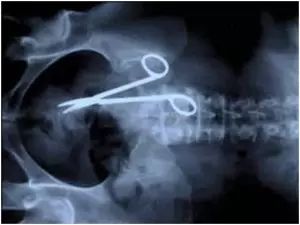

2.该病患在手术之后经常觉得腹痛,回到医院做透视发现上一次手术中医生把剪刀忘在他的肚子里了。(这就是艺术来源于生活的一个实例)

该病患在手术之后经常觉得腹痛,回到医院做透视发现上一次手术中医生把剪刀忘在他的肚子里了。